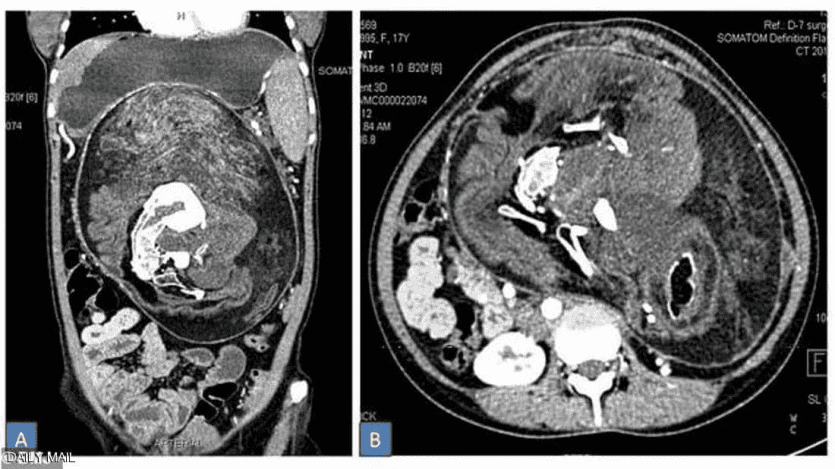

وبعد إجراء تصوير بالأشعة والتصوير المقطعي، اتضحت طبيعة الكتلة الغريبة داخل أحشاء الفتاة وتم التعرف عليها على أنها مجموعة كاملة من الأعضاء والأنسجة، وبدت بعض المناطق مثل الدهون، بينما ظهرت مناطق أخرى مثل الأنسجة الرخوة للأعضاء، ثم بعض الأجزاء الصلبة المكونة من الكالسيوم، والتي بدت بيضاء صارخة في التصوير بواسطة الأشعة المقطعية.

وعند الفحص الدقيق، تبين أن أجزاء الكالسيوم ما هي إلا عظام، وعلى وجه التحديد، فقرات وأضلاع وعظام طويلة.

كان ذلك قبل عامين، عندما قرر الأطباء إجراء عملية جراحية لإزالة هذه الكتلة، التي تبين أنها تحتوي بالفعل على العظام والشعر وعدة أسنان بالإضافة إلى "هياكل تشبه براعم الأطراف".